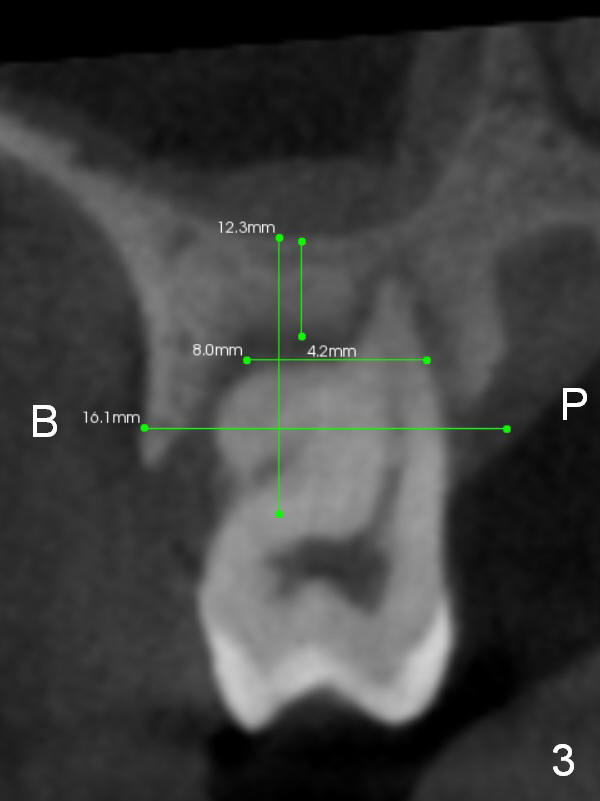

A 46-year-old lady is a typical dental phobic, but she is reasonable. Her chronic periodontitis is generalized and severe (Fig.1 3-D image, taken 1 year ago). An implant has been placed at #6 (healed site). It fails for the first time, probably due to bone loss after extraction. Soon after last periodontal maintenance, the tooth #2 develops pain and swelling. Immediate implant is a must.

The socket is wider buccopalatally (Fig.2 (3-D disto-occlusal view),3 (coronal section)) than mesiodistally (Fig.1,4 (sagittal section),5 (axial section)). Unless more bone loss has occurred in the last year, a 6x10 mm UF implant is to be placed in the middle of the socket (Fig.6, (soaked with 2% Xylocaine/1:50,000 Epinephrine gauze)) with bone graft to be placed in the buccal and palatal gaps (red circles). Bone density in the middle of the socket is 550-700 Hounsfield units. Use RT2 or 2 mm pilot drill to start osteotomy ~ 3 mm. The largest osteotome is RT4, or largest reamer 4 mm, followed by 4.5x17 mm tap at 14 mm, until 6x17 mm one. Make sure that the sinus floor is penetrated.